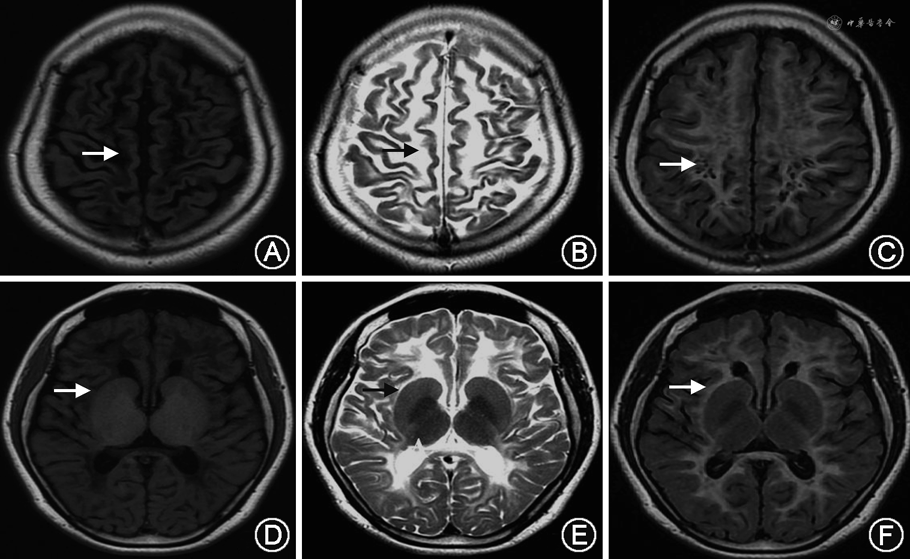

入院后检查结果:头颅MRI平扫:双侧脑室旁白质多发软化灶,周围弥漫型脱髓鞘,双小脑半球异常信号,伴脑萎缩(图1)。心电图:窦性心动过缓。胸部CT:右肺下叶条索灶。心脏超声、腹部超声及妇科超声均未见明显异常。认知量表:MoCA评分5分、MMSE评分 11分。全血铜:12.60 μmol/L(正常值7.12~21.29 μmol/L)、血清铜蓝蛋白:2.79 mg/L;青霉胺负荷试验阴性;双眼K-F环阴性。血尿便常规、肝肾功能、电解质、甲状腺功能、肿瘤系列、免疫功能、自身抗体、红细胞沉降率均未见明显异常。

VWM临床表型差异大,根据起病年龄及病程特点可分为先天型、婴儿型、早期儿童型、青少年型及成年型,其中以早期儿童型最为常见,VWM无确定的基因型-表型相关性[16]。2006年van der Knaap等[2]提出了VWM的临床诊断标准:(1)早期精神、运动发育基本正常或轻度落后;(2)儿童期出现进行性神经系统功能倒退,发热或轻微头部外伤均可引起病情加重;(3)神经系统症状主要包括肢体痉挛及小脑共济失调;(4)头颅MRI表现为弥散对称性大脑白质受累,白质异常在T1、T2及FLAIR像上逐渐演变为与脑脊液相同的信号。VWM有显著的头颅MRI特征[1,17, 18, 19],包括:(1)弥漫对称性脑白质广泛受累,累及中央区及皮质下白质。(2)白质异常在T1、T2及FLAIR像可逐渐变为与脑脊液相同的信号。(3)在T1加权像及FLAIR像可见在脑脊液样白质中有线状残存正常白质。(4)MRI上述异常可见于所有病例,即使无症状患者也有上述特点。(5)伴有轻到重度的小脑萎缩,主要累及蚓部。其中,最显著的特征为弥漫性大脑白质的液化现象。